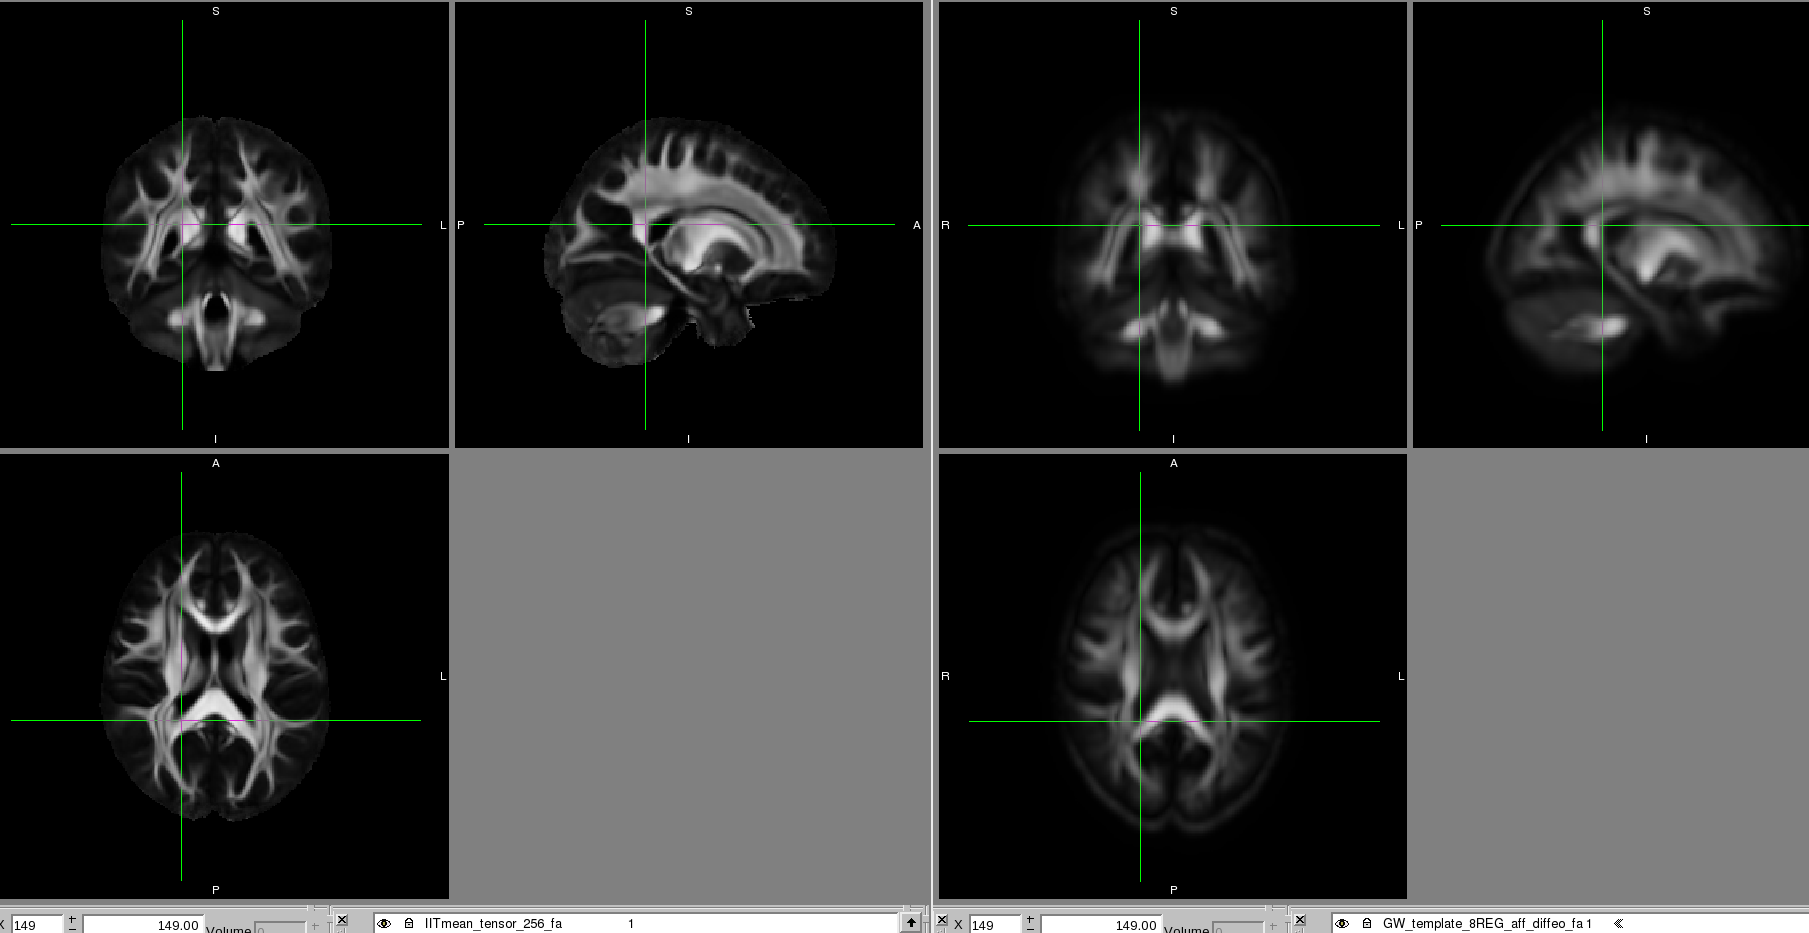

Please find attached a snap shot of the IIT atlas (left) and a single subject's template after deformable alignment to the IIT atlas (right).

I've tried registering my subject templates directly to the IIT atlas and still had the same problem.

I've also been trying to alter the regularisation parameters for

the diffeomorphic step which seems to have improved it in that it

looks more normal. Please find attached a screen shot of the IIT

atlas (left) and the group wise deformably aligned using

regularisation parameters 200 times the weaker ones provided.

There are still regions not well aligned with the IIT atlas and the image is quite blurry. We think this is because there is quite a lot of atrophy in the brains, particularly in the caudate as the are huntington's disease patients, and the ventricles are enlarged.